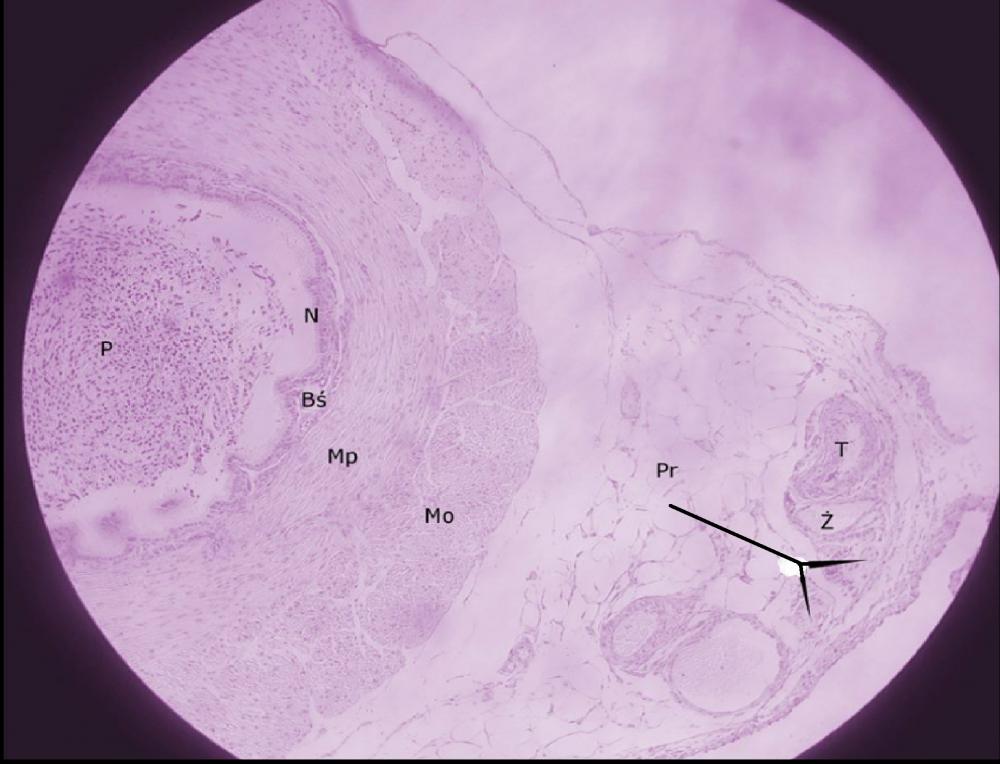

przydanka (nasieniowód)

tętnica (nasieniowód)

żyła (nasieniowód)

pnie nerwowe (nasieniowód)